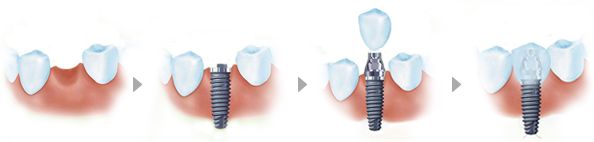

种植牙——种植牙是把种植体(人工牙根)通过一个小手术植入到牙槽骨中,然后在上面安装假牙的修复方式。由于人工牙相当于我们自然牙的牙根,可承受正常的咀嚼力量,功能和美观上几乎和自然牙一样,被称为人类的第三副牙齿。>>咨询一下:牙齿缺失修复要多少钱

优点:稳定牢固、美观舒适,不损伤周围正常的牙体组织,能承受近似真牙的咀嚼功能,寿命长。

缺点:种植牙修复后需要患者耐心的维护和清理,从而才能够维持更长时间。并且种植牙技术对医生、设备等要求很高,需选择专业的正规的口腔医院才能保证效果。